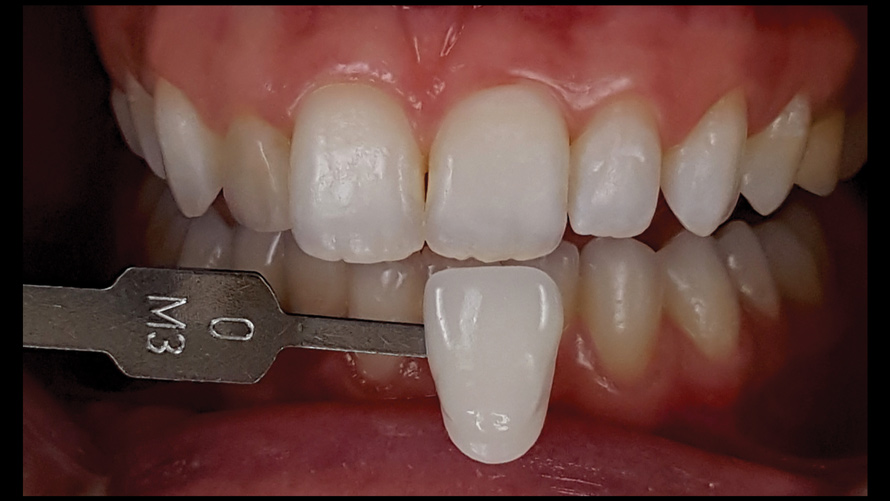

Shade Selection and Laboratory Communication

The most utilized intraoral photographs in the field of dentistry are perhaps those that capture shade information (Figure 18 and Figure 19). The analysis of color (ie, value, chroma, hue) in dentistry is a critical step in the fabrication of esthetic indirect restorations, such as all-ceramic crowns and porcelain laminate veneers. The ability to properly communicate this information with the dental laboratory is essential to ensure an appropriate shade match, a reduction in chairtime and overhead, and most importantly, a satisfactory patient experience and treatment outcome. In recent years, the use of polarized light photography as an aid in the shade selection process has become extremely popular. For some EALS devices, special polarizing filters have been specifically designed to fit over the light-emitting portion of the device (Figure 20 and Figure 21). The images produced using polarized light photography demonstrate an elimination or reduction in the specular reflection of hard and soft tissue, resulting in a matte-finish appearance of the dentition and gingiva. These types of photographs aid the ceramist in identifying areas of opacity and translucency, crack lines, hypo- or hypercalcification, and other internal features of the dentition that may not be readily visible without such a filter (Figure 22).

(18.) Tooth shade analysis of value, chroma, and hue taken with a smartphone and an EALS device.

Figure 18

(19.) Tooth shade analysis of value, chroma, and hue taken with a smartphone and an EALS device.

Figure 19